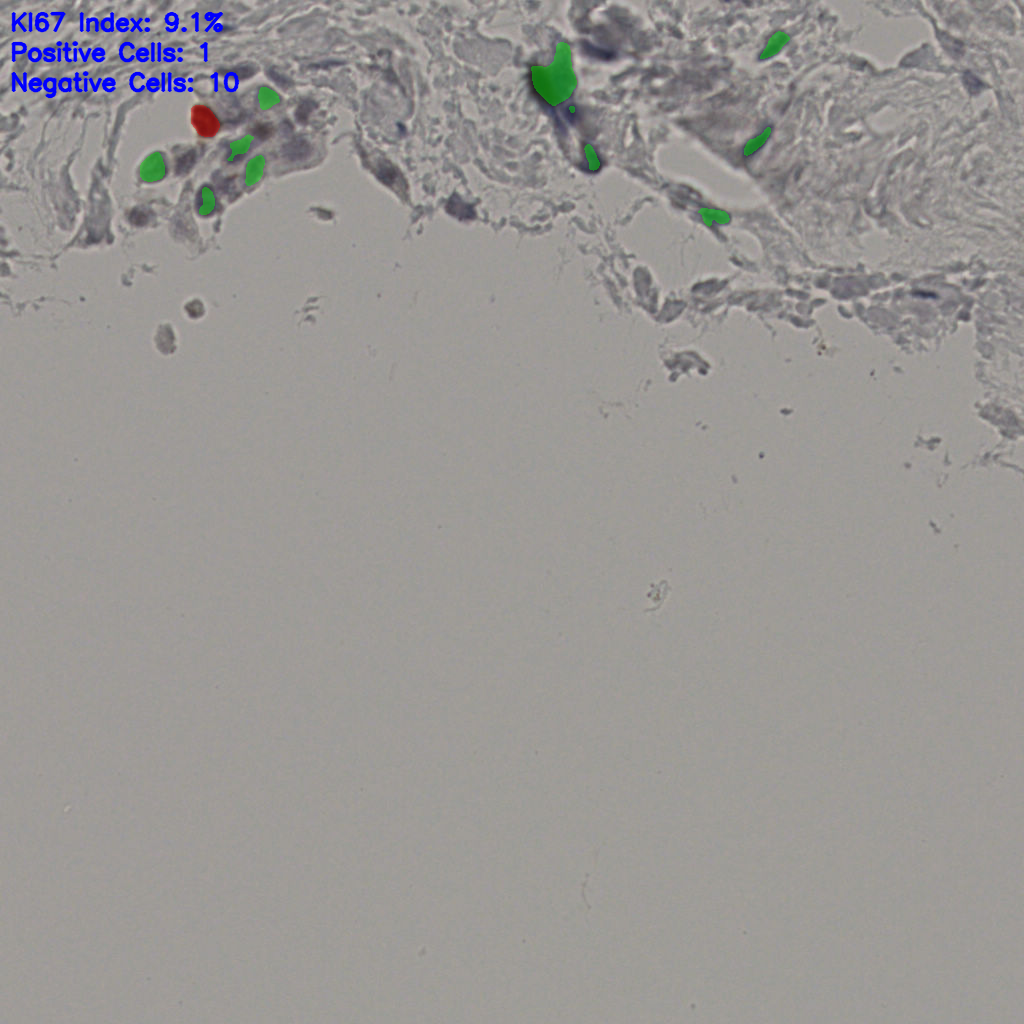

Ki67 指数

阴 19502

阳 1093